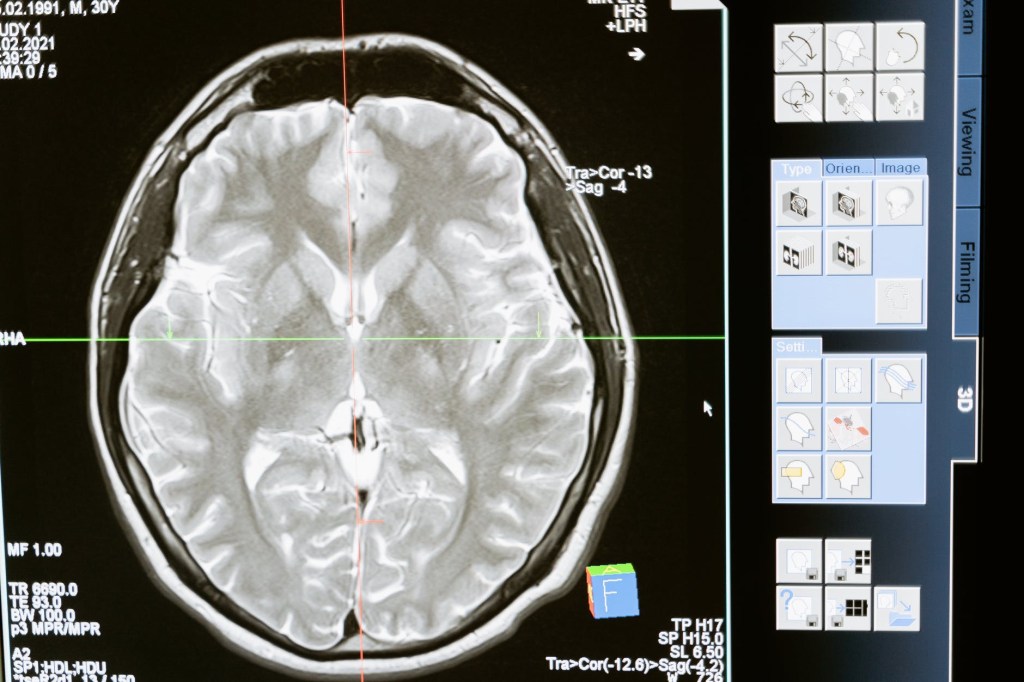

The same principle seems to apply to the brain.

People who are using their brain regularly with stimulating jobs are better off than people who are doing mind numbing jobs when it comes to dementia later in life.